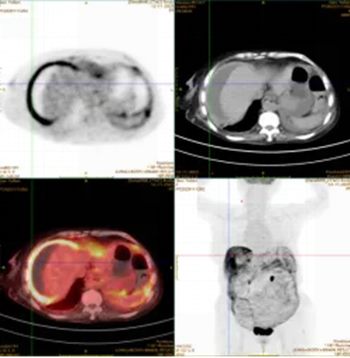

外院曾行诊断性腹腔穿刺,却未能明确病因。PET-CT检查提示恶性肿瘤可能。为寻求进一步诊治,家属来到医院胃肠甲状腺外科找到杨战锋主任。